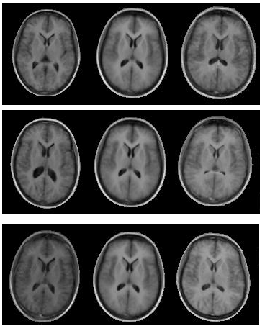

Figure: The effect of varying the first (top row), second, and third parameter of a brain appearance model by $\pm2.5$ standard deviations

Image aam_brain_set_modes_1-3

The effect of varying different elements of a combined model $\mathbf{c}$ for a model built from a set of 2-D MR brain images is shown in Figure [*]. The number of modes (columns) in $\mathbf{Q}_{s}$ and $\mathbf{Q}_{g}$ is one less than the number of images. In practice, it is often possible to approximate images pretty well, using fewer modes $m$.